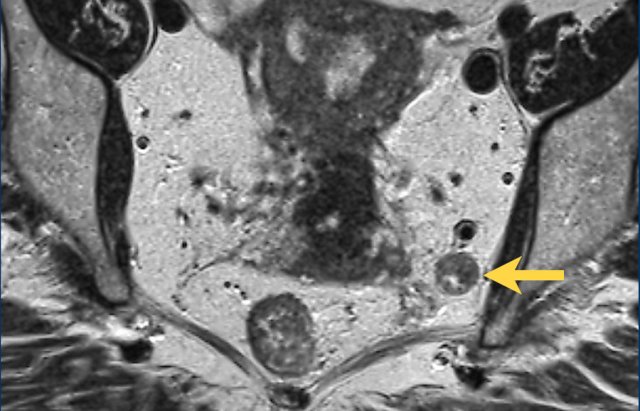

cT4a MRF-

The upper image shows a cT4a tumor in the upper rectum above

the level of the peritoneal reflection.

There is involvement of the peritoneum (yellow stippled line), but not of the

mesorectal fascia.

cT3 MRF+

The lower image shows a cT3 tumor in the low rectum below the

level of the peritoneal reflection.

There is involvement of the mesorectum on the anterior side

(green line), but not of the peritoneum.

cT4a MRF+

A combination of involvement of the peritoneum and the mesorectal fascia is also possible, like in this case.

This is a tumor in the upper rectum with involvement of the peritoneum on the anterior side and involvement of the mesorectal fascia on the posterior side.